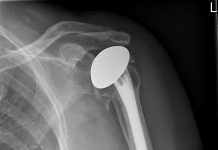

Rijnland Ziekenhuis plaatst eerste schouderprothese uit 3D-printer

Gisteren plaatste dr. Cornelis Visser, orthopeed in Rijnland Ziekenhuis, als eerste in Nederland een totale schouderprothese op maat. Voor de patiënt wordt een unieke mal...